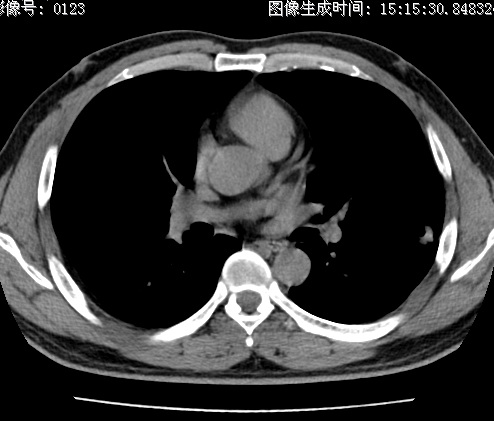

以下是引用zhao_bin2008在2010-1-4 20:15:00的发言:[br]先天性肺囊肿或小的肺隔离症?

以下是引用卜一在2010-1-4 22:09:00的发言:[br]先天性肺囊肿或小的肺隔离症?支持!

以下是引用zsl6918在2010-1-5 5:23:00的发言:[br]良性改变!肺囊肿,先天性支气管闭锁,血管畸形等均有可能。

以下是引用影像之路在2010-1-6 11:10:00的发言:[br]腺癌,最终的病检有些出乎意料之外,术前同志们大多考虑为肺囊肿或小的肺隔离征 [br]回过头来看 小结节呈分叶状,其内侧有一条较粗的静脉供血或许能成为支持诊断腺癌的理由